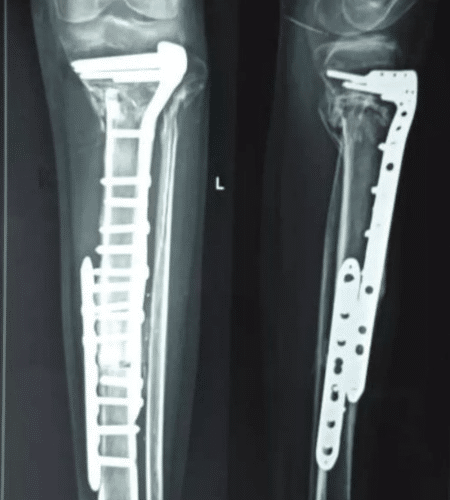

Yes. These are called “pathological fractures.” Specialized surgery can stabilize the bone using rods or prosthetics. This relieves severe pain almost immediately and helps the patient get back on their feet, rather than being bedridden. For more details visit Dr. Pradeep.

Not anymore. With advancements in technology and “Limb Salvage Surgery,” roughly 90-95% of patients can save their limbs. We remove the tumor and reconstruct the bone using metal implants or bone grafts, preserving both the appearance and function of the limb. For more details visit Dr. Pradeep.